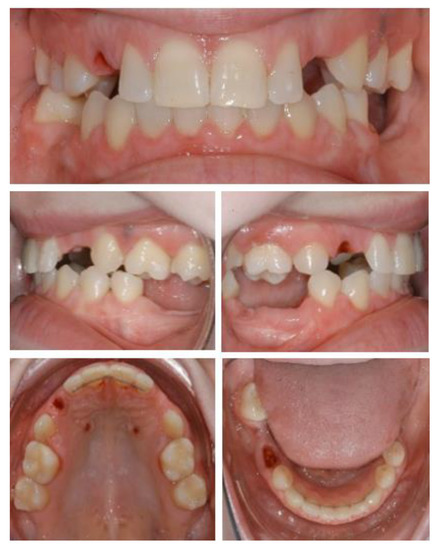

Figure 1.

Initial situation. Clinical examination showed absence of permanent teeth and persistence of primary dentition, abnormally shaped teeth, and unsatisfactory jaw relationship, suggesting the need of interdisciplinary treatment.